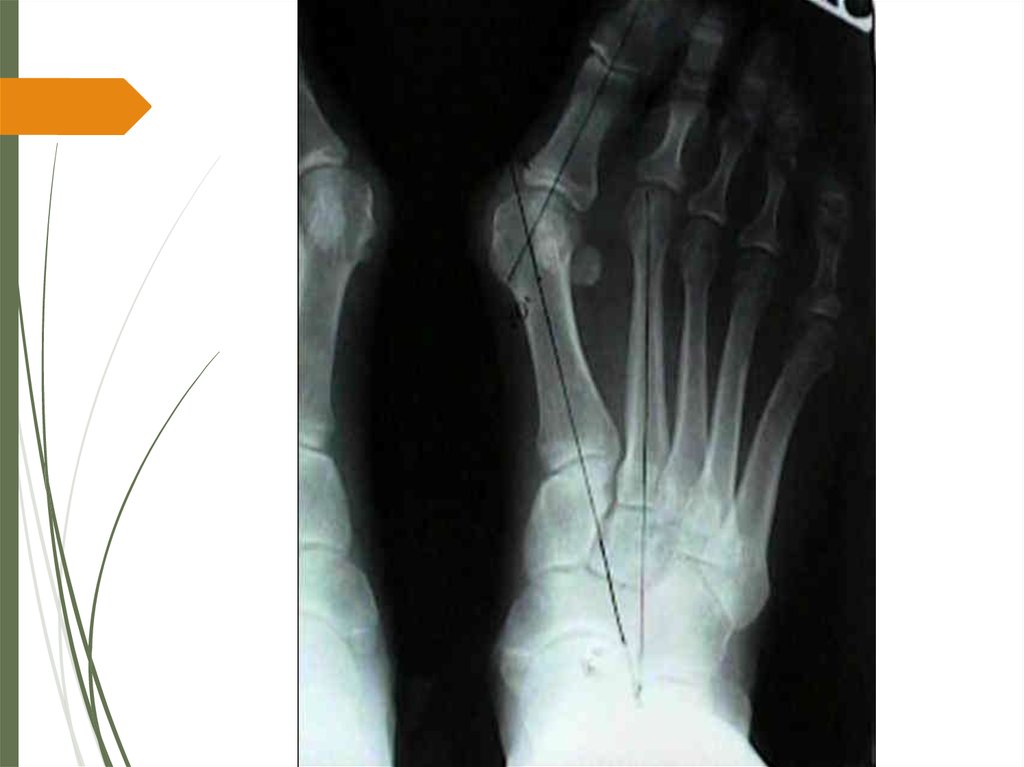

32. Операции на костях

Операции на костных структурах первого луча стопы

классифицируют по локализации зоны вмешательства

на резекционные артропластики, дистальные,

диафизарные и проксимальные остеотомии, артродез

медиального плюснеклиновидного сустава остеотомии

основной фаланги первого пальца стопы.